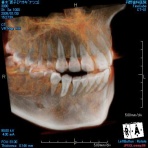

最新歯科用マイクロCTを導入しました!